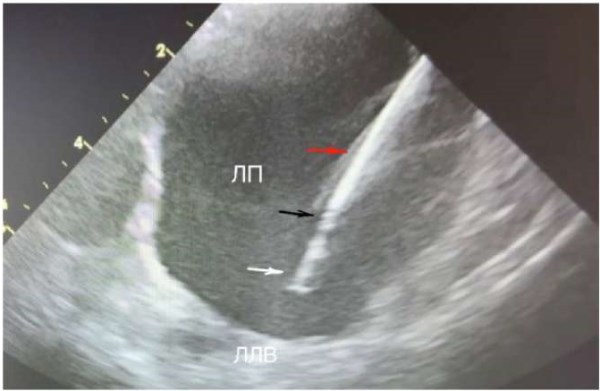

После проведения датчика в правое предсердие (ПП) его ось ориентируется на 12 ч (нос пациента в положении на спине без поворота головы), что отражается УЗ «домашней позицией», ориентиры ПП, трикуспидальный клапан, правый желудочек, корень аорты (рис. 2). Для безопасного позиционирования проводника транссептального интродьюсера необходимо визуализировать ВПВ. Следующее движение УЗ датчика — поворот по часовой стрелке на 3 ч. Анатомические ориентиры: ПП, левое предсердие (ЛП), межпредсердная перегородка, корень аорты, из этой позиции визуализируется ушко ЛП (рис. 3), при отсутствии признаков тромбоза принимается окончательное решение о проведении процедуры в ЛП. Для выведения ВПВ с помощью верхнего и нижнего колец управления луч датчика поворачивается кзади и вправо на 45°. Анатомические ориентиры: ВПВ, восходящая аорта, ЛП. Проводник через НПВ, ПП заводится в ВПВ под УЗ контролем и далее по нему транссептальный интродьюсер (рис. 4). После замены проводника на транссептальную иглу управляющие кольца УЗ датчика возвращаются в нейтральную позицию для визуализации межпредсердной перегородки, интродьюсер с иглой смещается вниз на овальную ямку. При затруднении пункции телом иглы возможна пункция внутренним стилетом с дальнейшим поэтапным проведением иглы на стилет, дилататора на иглу, интродьюсера на дилататор (рис. 5). По проведенному через интродьюсер в левую верхнюю ЛВ жёсткому проводнику проводится смена интродьюсера на доставляющее устройство для криобаллона. Выведенный за пределы доставляющего устройства баллон и циркулярный катетер хорошо определяются визуально (рис. 5), также показателем выведения баллона является метка на катетере. Управляя УЗ катетером вращением по и против часовой стрелки, а также с помощью управляющих колец изгибая катетер вперёд-назад и вправо-влево выводятся поочерёдно (по часовой стрелке) левые ЛВ, далее правая нижняя и правая верхняя ЛВ (рис. 6, 7). Стимуляционный катетер проводится в правый желудочек из «домашней позиции», а ВПВ по описанной ранее методике. Контроль окклюзии УЛВ осуществляется с помощью цветной допплероскопии (рис. 8, 9) и «пузырьковой пробы», для чего в просвет криобаллонного катетера вводится физиологический раствор. Контроль полости перикарда проводится из ПП (поворот из «домашней позиции» против часовой стрелки) и из правого желудочка (загибание управляющим кольцом кпереди), эту манипуляцию мы проводим как во время процедуры, так и перед завершением и извлечением УЗ катетера.

Рис. 5. Буж и шифт в полости ЛП. Белой стрелкой указан буж, красной — шифт, черной — граница между шифтом и бужом.

Сокращения: ЛЛВ — левая легочная вена, ЛП — левое предсердие.